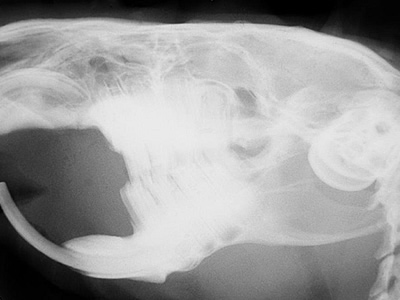

- Hier seht ihr das Röntgenbild eines Meerschweinchen-kopfes. (c) Dr. med.vet. Jochen Krüger www.tierzahn.de